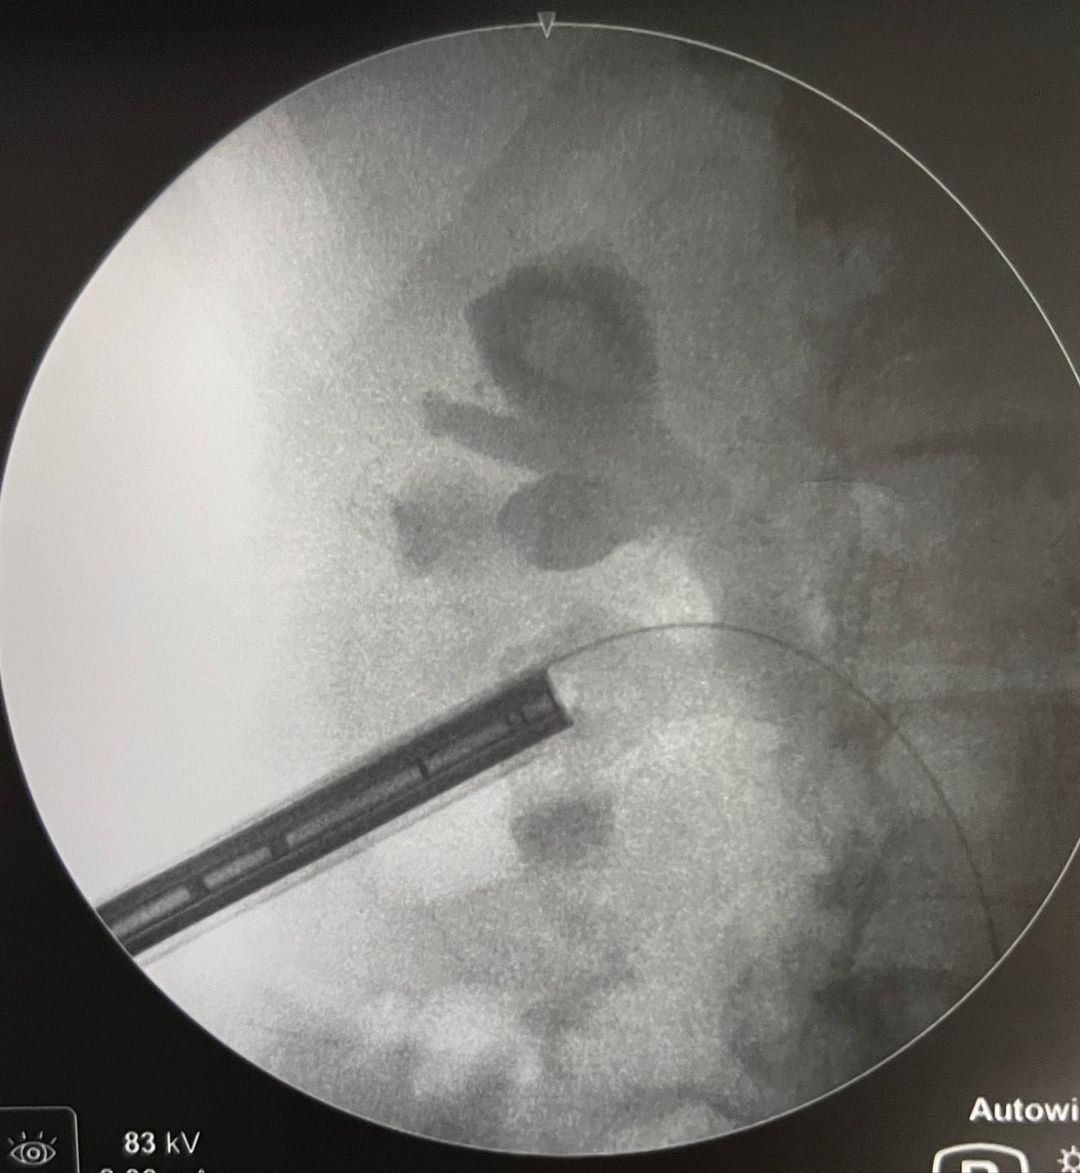

Especialista em Cirurgias Urológicas Minimamente Invasivas, com destaque para Cálculos Renais e Tumores Urológicos.

Imagens